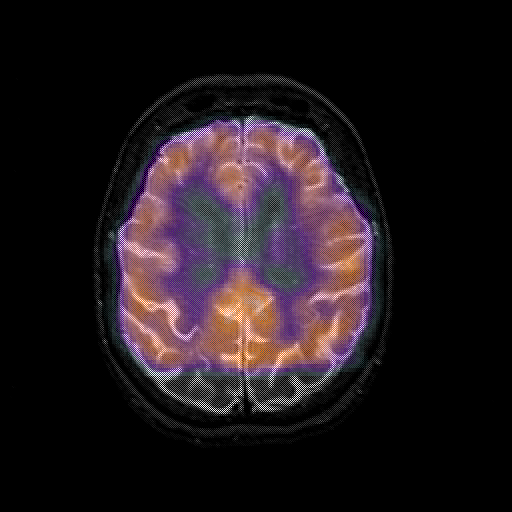

overlay: Slice 37

Slice 37

MRCBFCBF with

T1PDT2T1PDT2